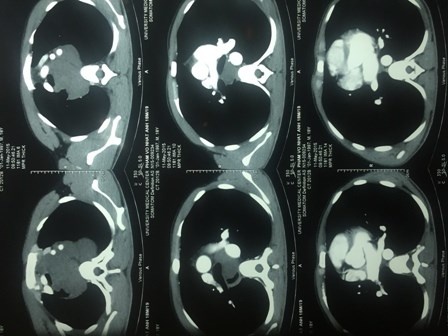

| Chụp CT- Scan phát hiện bệnh nhân có khối u lớn ở vùng trung thất. |

Trước đó, bệnh nhân P. V. N. A. (sinh năm 1997, ở Cần Giờ, TP HCM) đến khám tại bệnh viện vì có cảm giác vướng khi nuốt và khó thở khi nằm. Tình trạng này kéo dài gần một tháng và bệnh nhân đã đi khám ở nhiều bệnh viện nhưng không tìm ra bệnh. Qua thăm khám, các bác sĩ phát hiện bệnh nhân có khối u lớn ở vùng trung thất gây chèn ép vào đường ăn và đường thở. Bệnh nhân được sinh thiết, kết quả cho thấy bệnh nhân bị u sợi thần kinh khổng lồ chiếm toàn bộ vùng cổ và trung thất sau. Khối u bao quanh các mạch máu lớn vùng trung thất và dính với thực quản.